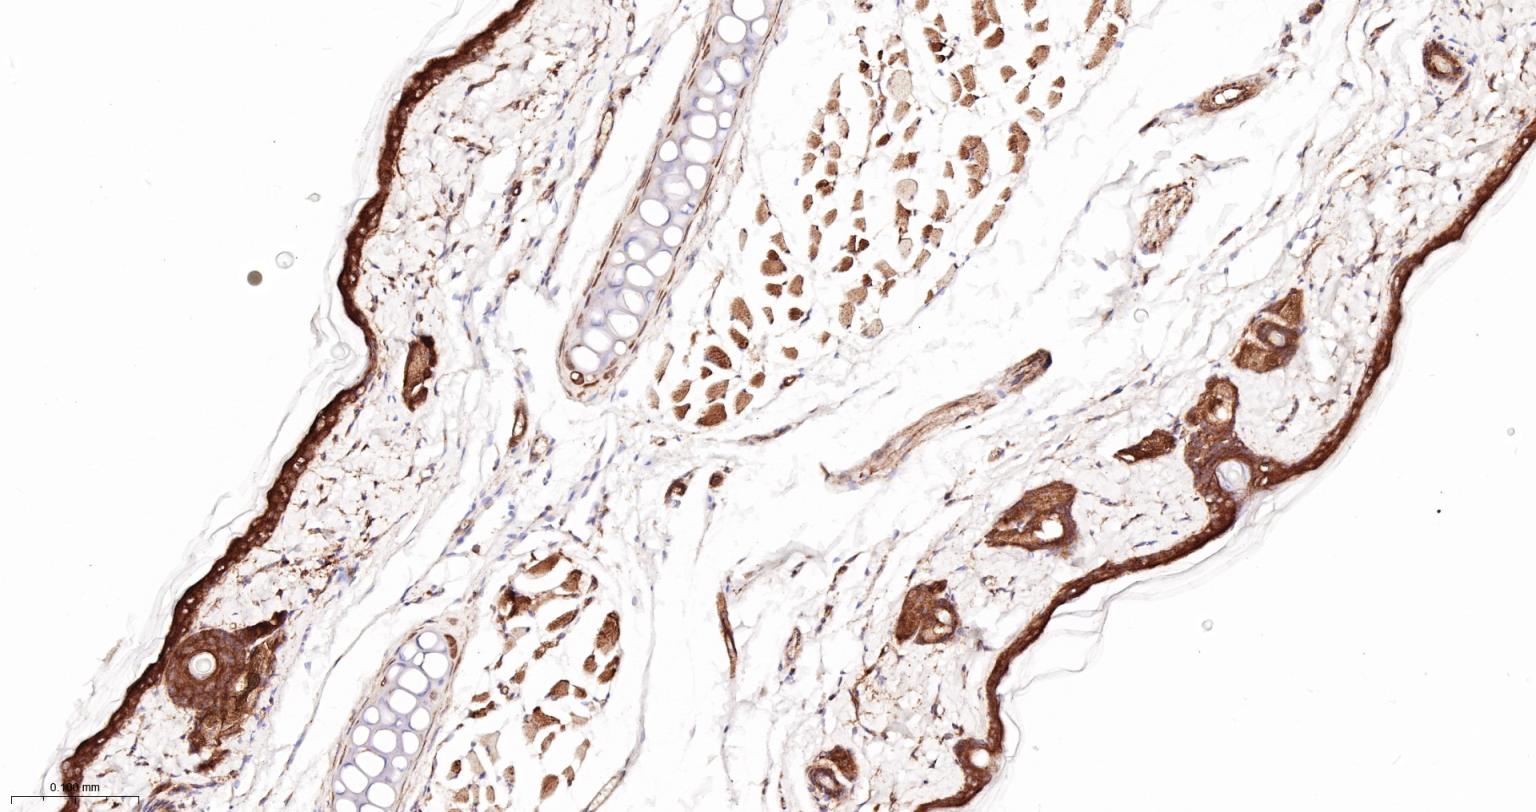

Paraformaldehyde-fixed, paraffin embedded Human Skin; Antigen retrieval by boiling in sodium citrate buffer (pH6.0) for 15 min; The section was incubated with ARP2 Monoclonal Antibody, Unconjugated (bsm-62309R) at 1:200 overnight at 4°C, followed by conjugation to the bs-0295G-HRP and DAB (C-0010) staining.

Paraformaldehyde-fixed, paraffin embedded Rat Skin; Antigen retrieval by boiling in sodium citrate buffer (pH6.0) for 15 min; The section was incubated with ARP2 Monoclonal Antibody, Unconjugated (bsm-62309R) at 1:200 overnight at 4°C, followed by conjugation to the bs-0295G-HRP and DAB (C-0010) staining.